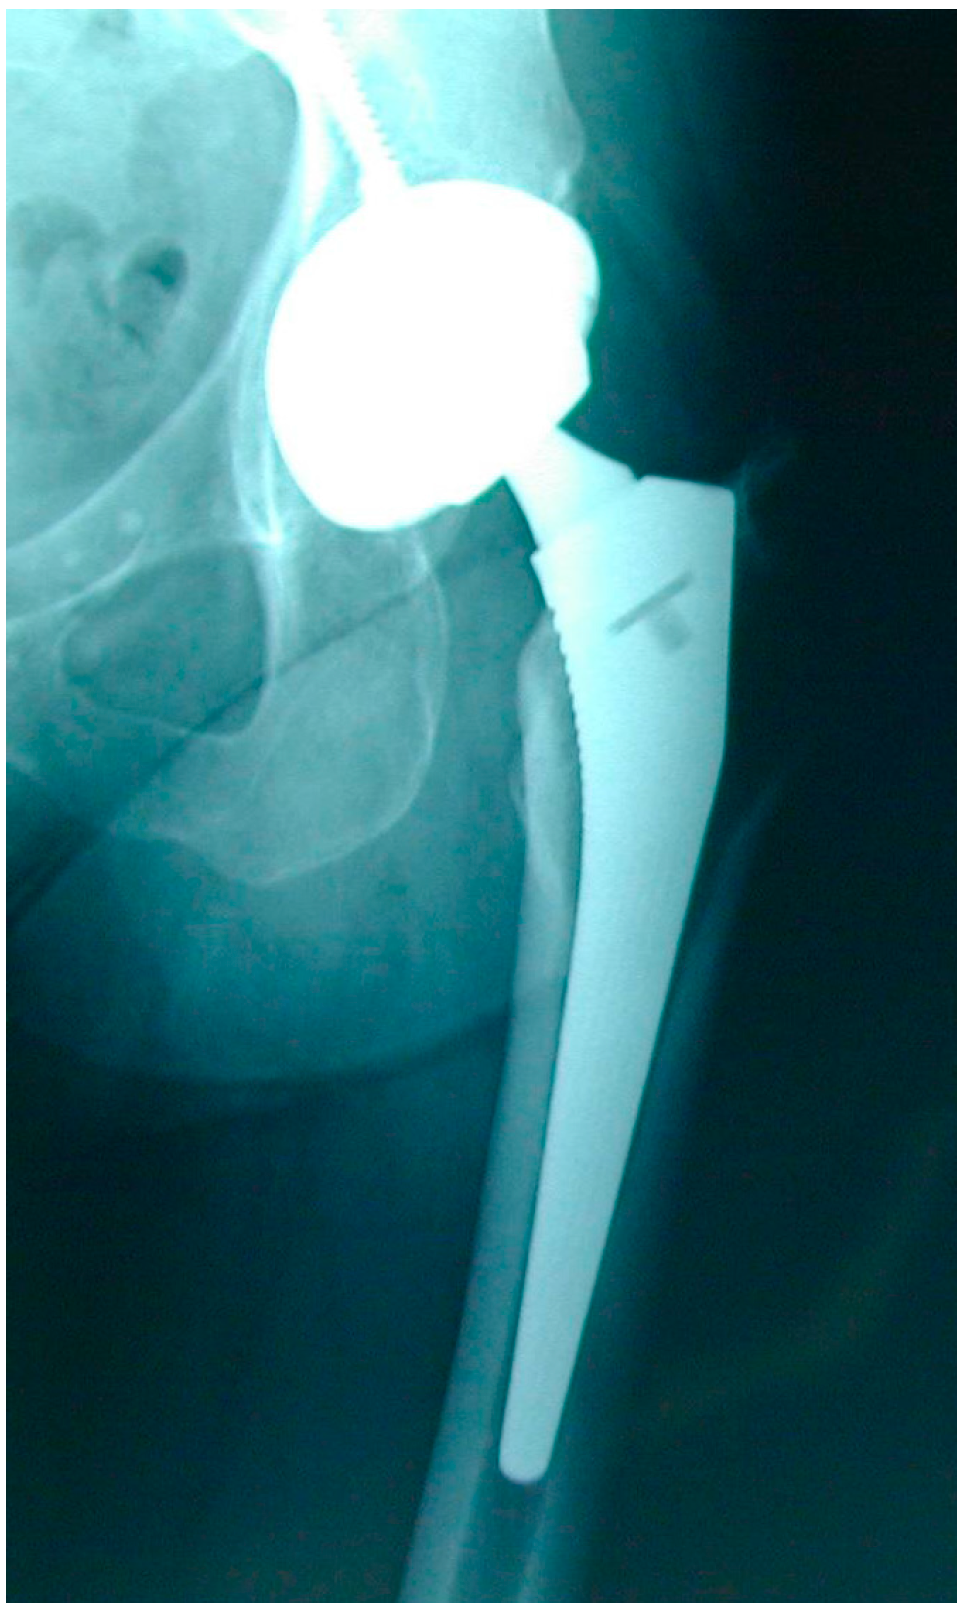

Early HRA failure modes mainly consisted of femoral neck fractures [11] (Figure 2), treated by revising only the femoral component and preserving the acetabular component and the MoM bearing. Large diameter MoM femoral heads modularly fitting on a prosthetic femoral stem had been specifically designed for these femoral component-only revisions of HRA (Figure 3). Following the good initial results of the Metasul® MoM hips and the reduced risk of dislocation with large diameter femoral heads, these HRA revision big femoral head (BFH) components were also used for primary THA, despite the smaller coverage angle of the acetabular design, the introduction of an additional MoM articulation at the taper–trunnion head–neck junction and despite the fact that these components had not been thoroughly tested for this indication [12,13].

Figure 3.

MoM total hip arthroplasty with large diameter femoral head.